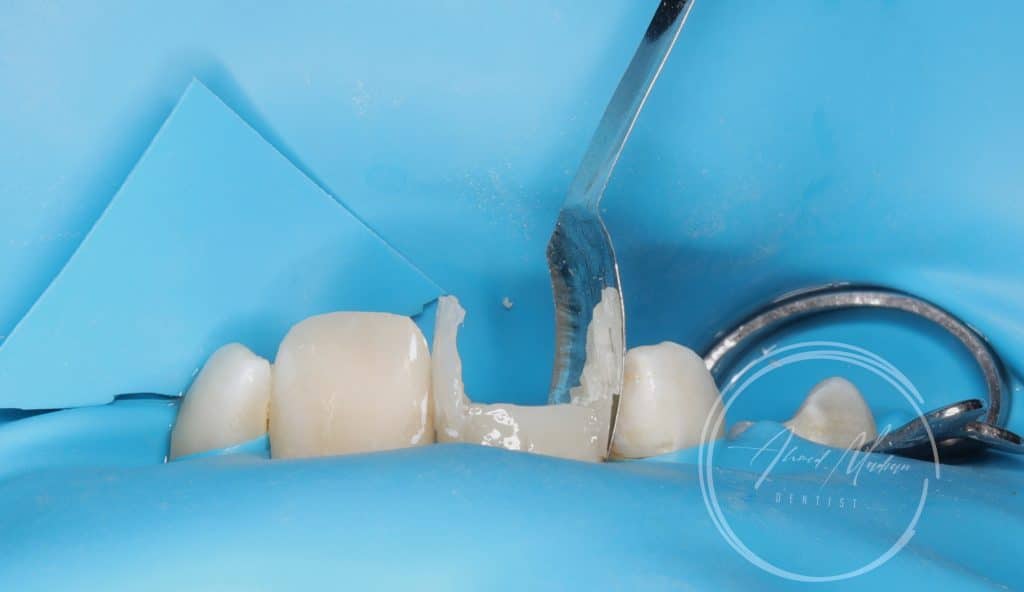

11 – gingivectomy , DME , build up , cleaning and shaping , intra canal medication and patient will be under follow up for the next month considering the initiation of internal or external resorption , after follow up RCT , fiber post will be placed

12 – direct composite restoration